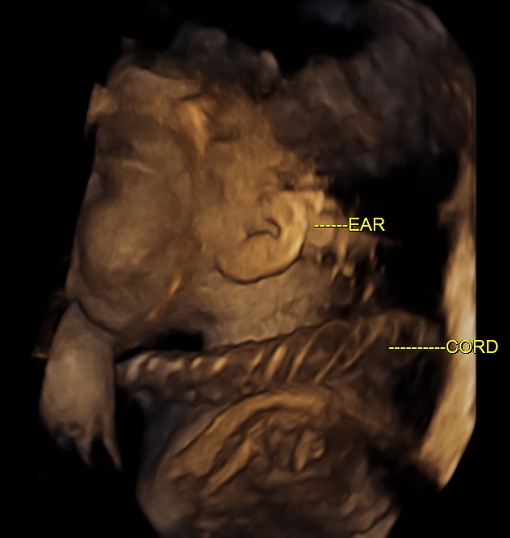

Babys Cord Cords Neck Nuchal Truth Umbilical The Truth